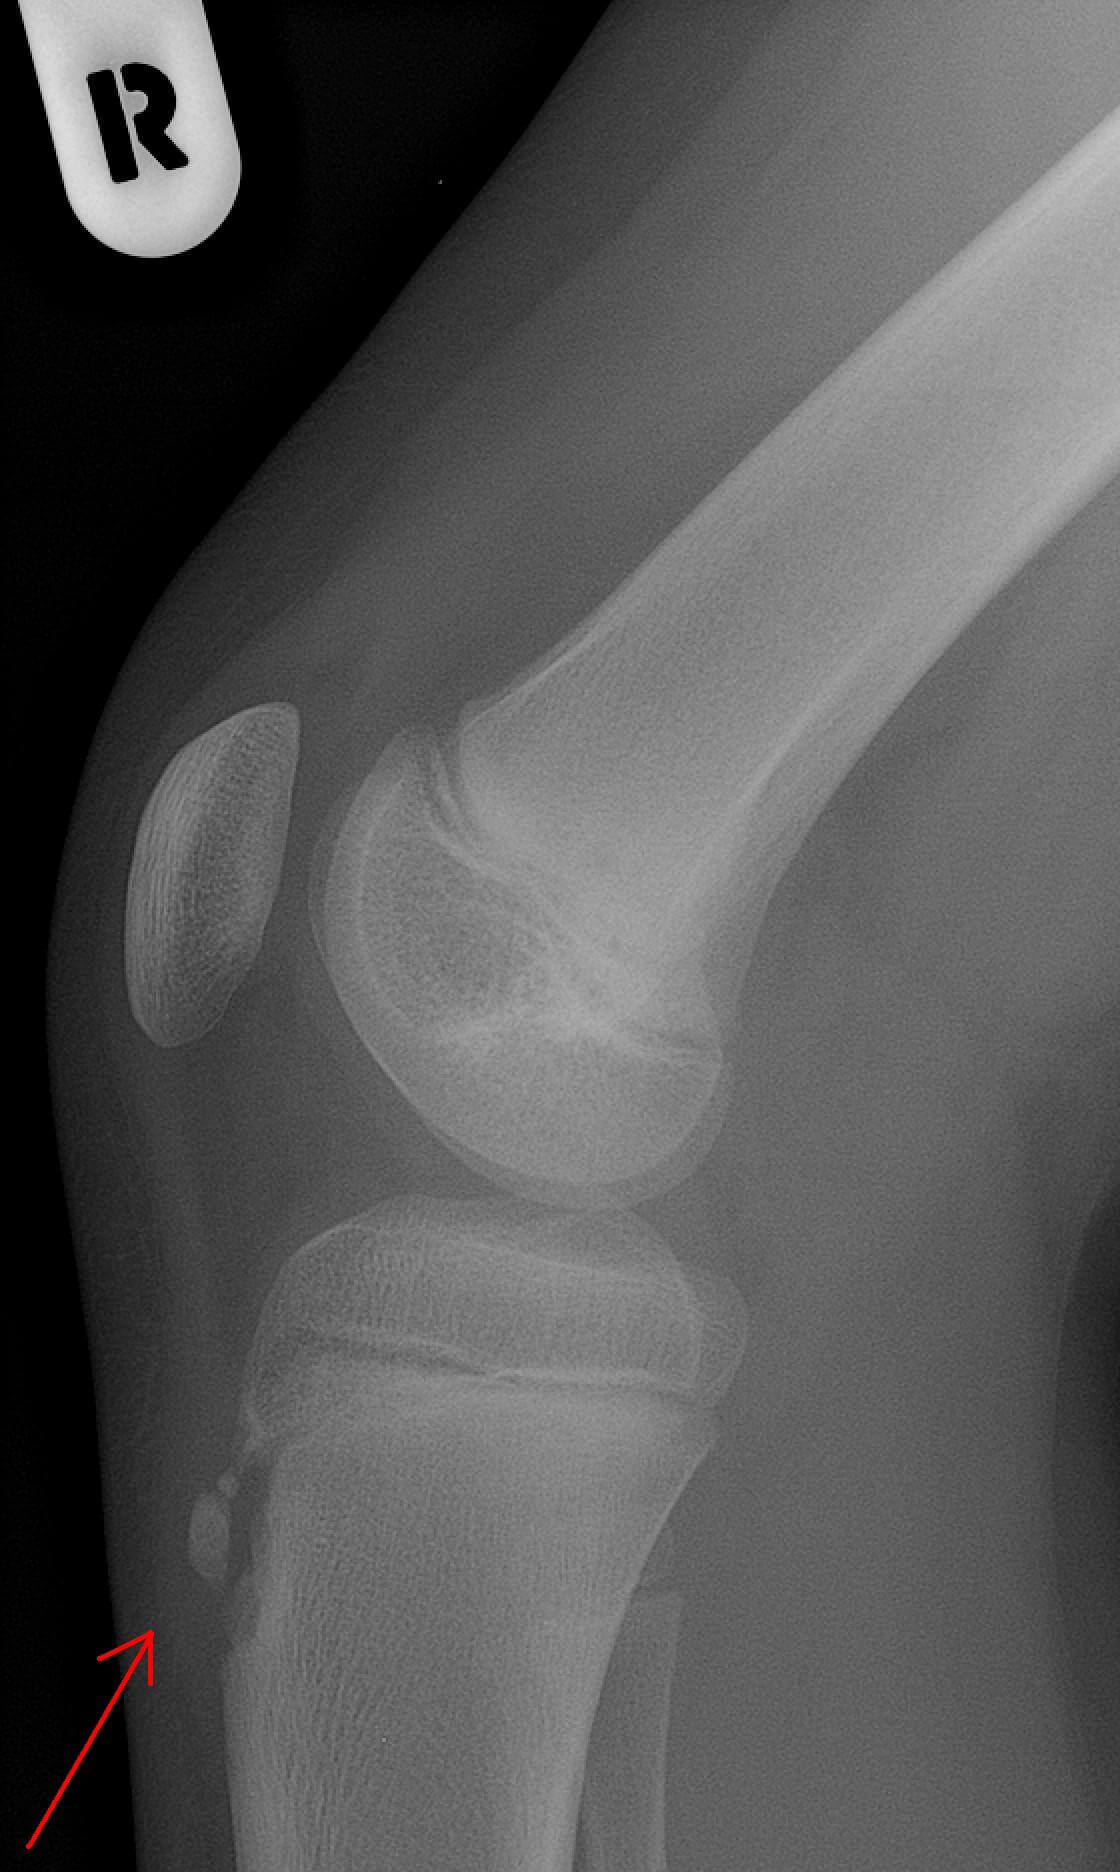

・膝の下がぽっこり腫れ上がる